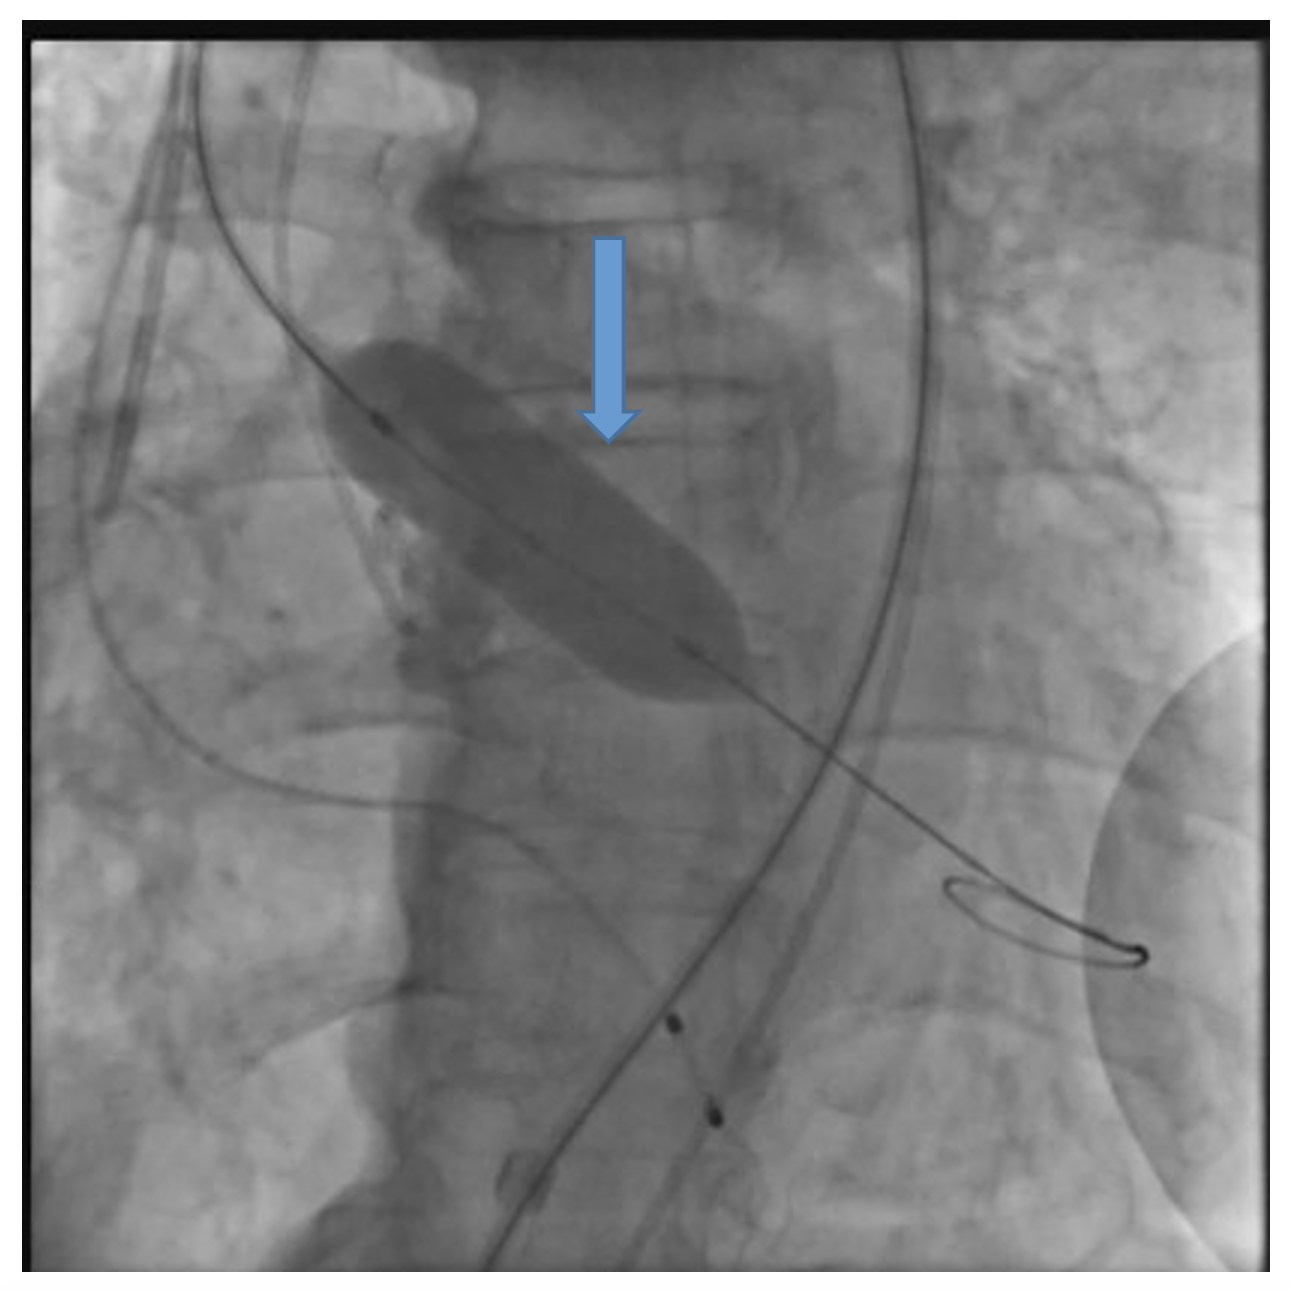

The patient was taken up for TAVR via a left common femoral artery (CFA) approach. The aortic valve was crossed (Figure 1A), and pre-dilatation was done using an 18-mm x 40-mm Mammoth balloon catheter (Meril Life Sciences) (Figure 1B). A 24.5-mm Myval transaortic valve (Meril Life Sciences) was introduced inside a Python expandable introducer sheath (Meril Life Sciences). However, the device could not be negotiated in the distal external iliac artery (EIA) due to calcium. The arrow in Figure 2A shows calcium in the distal EIA. The artery forceps depicts a marker for the distal end of the Python sheath. The sheath was withdrawn in the distal EIA; right CFA puncture was done and a 7F crossover sheath was placed. Intravascular lithotripsy (IVL) was done using a 7-mm x 60-mm IVL balloon; 30 pulses at 4 atm followed by 30 pulses at 6 atm were given (Figure 2B).